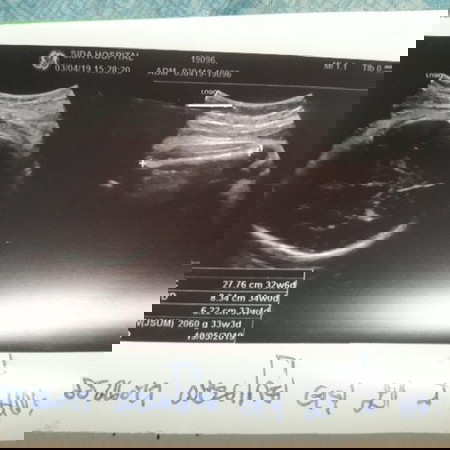

ผลอัลตร้าซาวด์..

ตอนนี้ ตั้งครรถ์ ได้ 36 สัปดาห์ ไปอัลตร้าซาวด์มา หมอบอกลูกตัวเล็กมาก น้ำหนักไม่ถึง 2500 กรัม มีผลต่อลูกในครรถ์มั้ยค่ะ